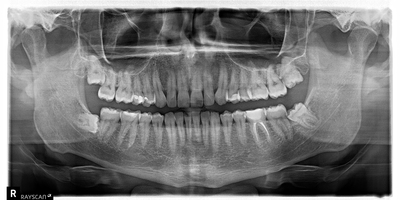

Снимок ниже сделан сразу после операции.

Дальше задача наблюдать и ждать, пока костная ткань в этой области восстановится.

После удаления было проведено несколько осмотров, снятие швов – все как обычно. Через месяц – контрольный снимок.

Что мы видим? Темное пятно в области проведенной операции сохраняется, что нормально, потому как прошел всего месяц с момента удаления. Заживление проходит хорошо, каких-либо проблем в восстановлении не наблюдается. Не зря я отметил пунктиром область зуба мудрости с противоположной стороны, потому как там есть точно такая же фолликулярная киста, как и слева, но на начальных этапах своего роста.